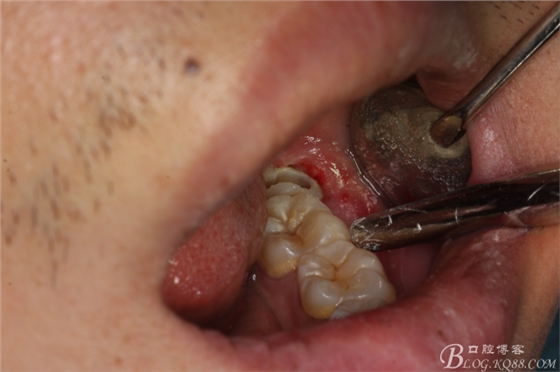

圖1.口內(nèi)觀:38牙冠萌出約1/3,頰側(cè)牙齦輕度紅腫,牙冠低于37合面,屬于中位阻生

圖4.采用不切開(kāi)、不翻瓣、利用暴露出來(lái)的牙冠進(jìn)行潛掘式分牙